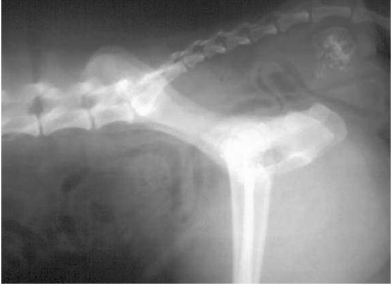

Which one of the following statements best represents the features present on this lateral radiograph of the cranial abdomen and thorax?

This is a cat with a normal liver and stomach